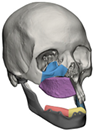

| 3 | 41 | FO-M3 * | ![]() | Glenoid fossa and complete left hemimandible | Alloyed titanium backing capping the UHMWPE fossa | Cobalt-chromiun-molybdenum alloy condylar head and Titanium alloy body consisting of two interloching pieces | Skull component: 52.0 mm titanium screws. Manibular component: 112.7 mm titanium screws |